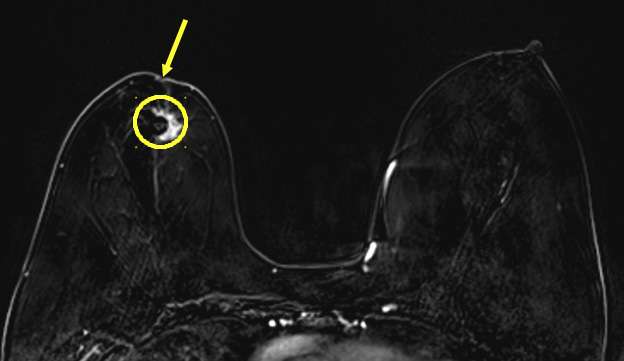

MRI: Provides detailed images demonstrating the extent of skin involvement and characteristics of a potential underlying malignancy.